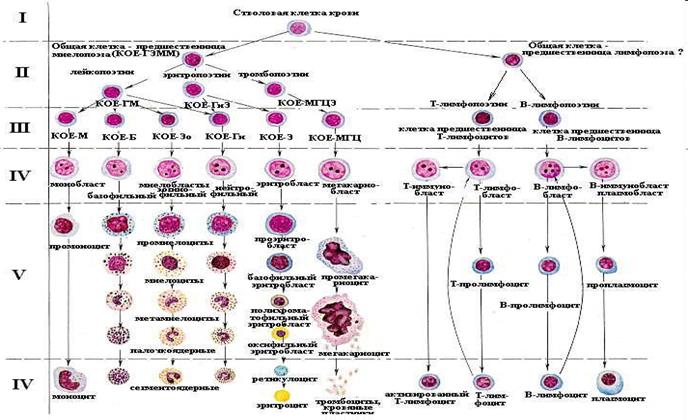

Гемопоез – фізіологічний процес утворення, розвитку та дозрівання клітин крові.

І клас – стовбурові клітини – дають початок всім форменим елементам крові.

ІІ клас – уніпотентні клітини – дають початок двум направленням: мієлопоез та лімфопоез.

ІІІ клас – розвиваються по одному направленню, дають 8 початків утворення клітин крові.

ІV клас – бласти, клітини крові морфологічно відрізняються між собою.

V клас – дозріваючі клітини.

VІ клас – зрілі клітини.

При гострому лейкозі спостерігається збільшення клітин класу 1 – 3.

При хронічному лейкозі спостерігається збільшення баластних клітин.